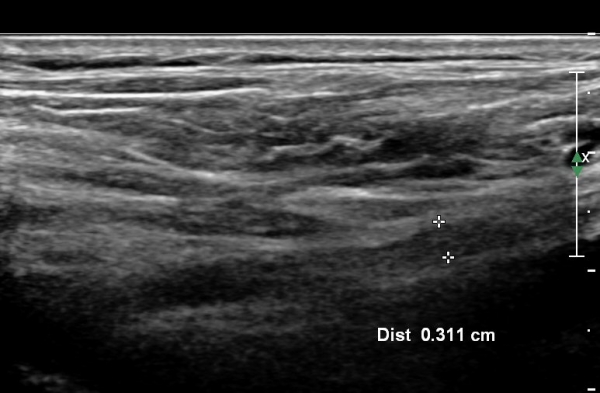

ÃÊÀ½ÆÄ °Ë»ç :  ÁÂÃø ¸ñ ¾Õ ¿ÜÃø¿¡¼­ °üÂûÇÑ Á¦5°æÃß ½Å°æ±Ù Ⱦ´Ü¸é°Ë»ç¿¡¼­ Á¦5°æÃß ½Å°æ±ÙÀÇ °æ¹ÌÇÑ Àú¿¡ÄÚ

ºÎÁ¾ÀÌ °üÂûµÊ(»çÁø 1).